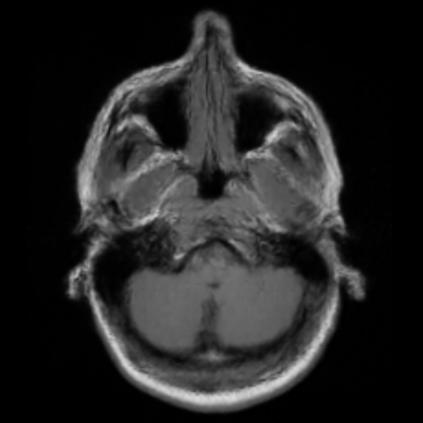

Motion artifacts are a primary source of magnetic resonance (MR) image quality deterioration with strong repercussions on diagnostic performance. Currently, MR motion correction is carried out either prospectively, with the help of motion tracking systems, or retrospectively by mainly utilizing computationally expensive iterative algorithms. In this paper, we utilize a novel adversarial framework, titled MedGAN, for the joint retrospective correction of rigid and non-rigid motion artifacts in different body regions and without the need for a reference image. MedGAN utilizes a unique combination of non-adversarial losses and a novel generator architecture to capture the textures and fine-detailed structures of the desired artifacts-free MR images. Quantitative and qualitative comparisons with other adversarial techniques have illustrated the proposed model's superior performance.

翻译:移动文物是磁共振(MR)图像质量恶化的一个主要来源,对诊断性能产生强烈影响。目前,MR运动的校正要么是预期性的,借助运动跟踪系统,要么是追溯性的,主要是利用成本昂贵的计算迭代算法。在本文中,我们使用名为MedGAN的新颖的对抗性框架,联合追溯性地校正不同身体区域的硬性和非硬性运动文物,而不需要参考图像。 MedGAN利用非对抗性损失和新型生成器结构的独特组合来捕捉无MR图象的纹理和精细详细结构。 与其他对抗性技术的定量和定性比较展示了拟议模型的优异性表现。